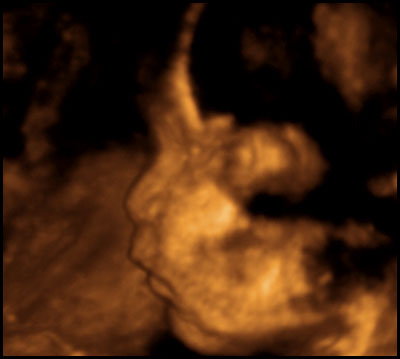

First, some notes on what you're seeing, in case some of these graphics seem a little weird. The machine only captures 3D images in a small area, and anything outside the area is either not visible or appears as blurriness. Also, while the technician tried for a good face shot, the baby's head was partially smooshed against the placenta the whole time, so it was never possible to get a really clear eyes/nose/mouth image.

Anyway, here he is....toes and all.